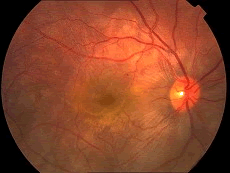

男,6岁,其家长诉患儿喜眯眼视远。视力:右0.4,左0.1,眼前后节检查未发现明显异常。其睫状肌麻痹下验光结果为:右 +5.00DS+1.00DC×90°=0.6,左 +5.00DS+1.00DC×85°=0.6,应诊断为()

女,5岁,两岁发现内斜视。检查:视力为右0.3,左0.1,眼位为左眼+15°,眼球运动为各方向均不受限。眼底像清晰未发现明显异常,同视机检查不合作,睫状肌麻痹下验光结果为中度远视,下一步如何处理()